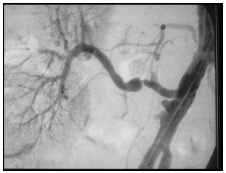

Paciente transplantado renal em 2006, a partir de um doador cadáver, com tempo de isquemia fria de 34 horas, leva quase 2 semanas para reestabelecer a função renal. Evoluindo bem a partir de então, até apresentar há 4 meses um episódio de rejeição revertido com altas doses de corticoide. Em seguida, o mesmo começa a ter importantes picos hipertensivos de controle difícil com tratamento medicamentoso e queda da função renal. Nefrologista que acompanha o paciente solicita ultrassom do rim transplantado que está normal. É então feito arteriografia renal, conforme ilustração abaixo, e uma biópsia do rim transplantado. Marque a alternativa INCORRETA .

Os picos hipertensivos apresentados pelo paciente são explicados pelo achado de estenose da artéria renal na arteriografia, de origem imunológica, secundários aos episódios de rejeição aos quais ele foi submetido.